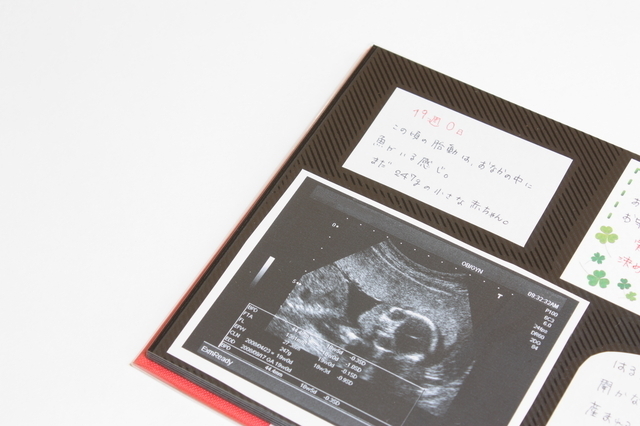

この時期になると初めての胎動を感じるママも出てきます。胎児のパンチやキックが、胎動としてママに伝わります。

胎児はまだ小さく力も弱いので、はっきりと感じられないかもしれませんが、子宮の内側に胎児が当たったのを感じることができます。

胎児は子宮の中を漂っているので、それにともない胎動を感じる場所も変わってきます。胎動の感じ方には個人差があるので、まだ感じられなくとも神経質になる必要はありません。